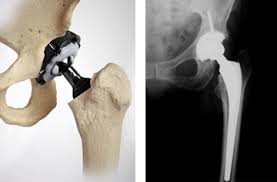

Prótesis total de cadera.

¿QUÉ ES UNA PRÓTESIS TOTAL DE CADERA?

La prótesis total de cadera es uno de los mayores adelantos de la cirugía ortopédica de este siglo. El pioneros en su diseño y utilización fue Sir John Charnley, un cirujano ortopédico que, con la colaboración de un equipo de ingenieros, desarrolló la técnica y los materiales utilizados en la prótesis total de cadera. Esta técnica supone la sustitución de una articulación artrósica o lesionada por una articulación artificial denominada prótesis.